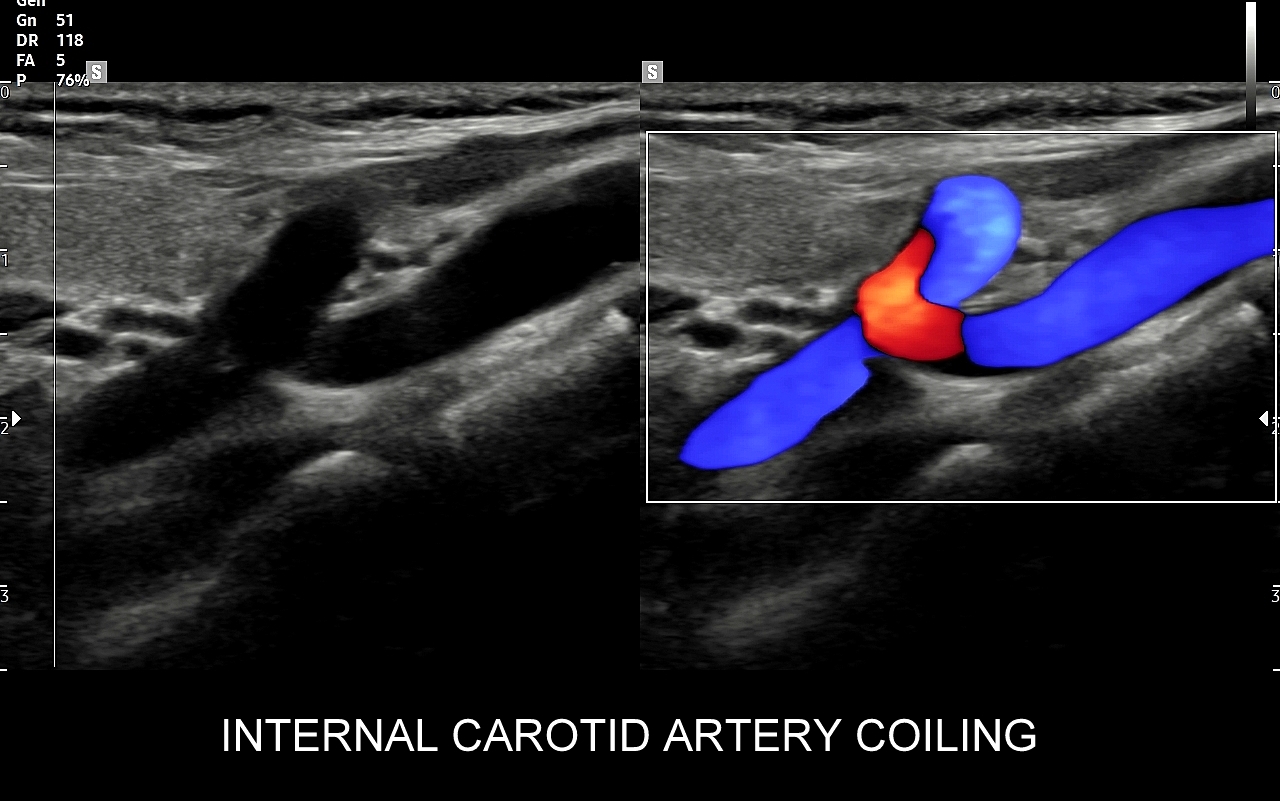

Badanie USG Doppler tętnic szyjnych i kręgowych, określane również jako badanie USG tętnic dogłowowych, to najczęściej wykonywane badanie diagnostyczne w układzie tętniczym. Wynika to z faktu, iż wymienione naczynia doprowadzają krew do jednego z najważniejszych organów człowieka, tj. mózgu, a choroby lokalizujące się w tętnicach dogłowowych mogą być źródłem różnorodnych objawów neurologicznych począwszy od zaburzeń pamięci i widzenia, poprzez bóle i zawroty głowy, aż do zgonu na tle nagłego udaru niedokrwiennego. W trakcie standardowego badania USG tętnic dogłowowych oceniane po obu stronach są tętnice szyjne wspólne, wewnętrzne, zewnętrzne oraz tętnice kręgowe. Badanie niejednokrotnie rozszerza się o specjalistyczną ocenę USG łuku aorty, USG tętnic podobojczykowych, USG tętnic skroniowych, czy o badanie USG Doppler przezczaszkowy.